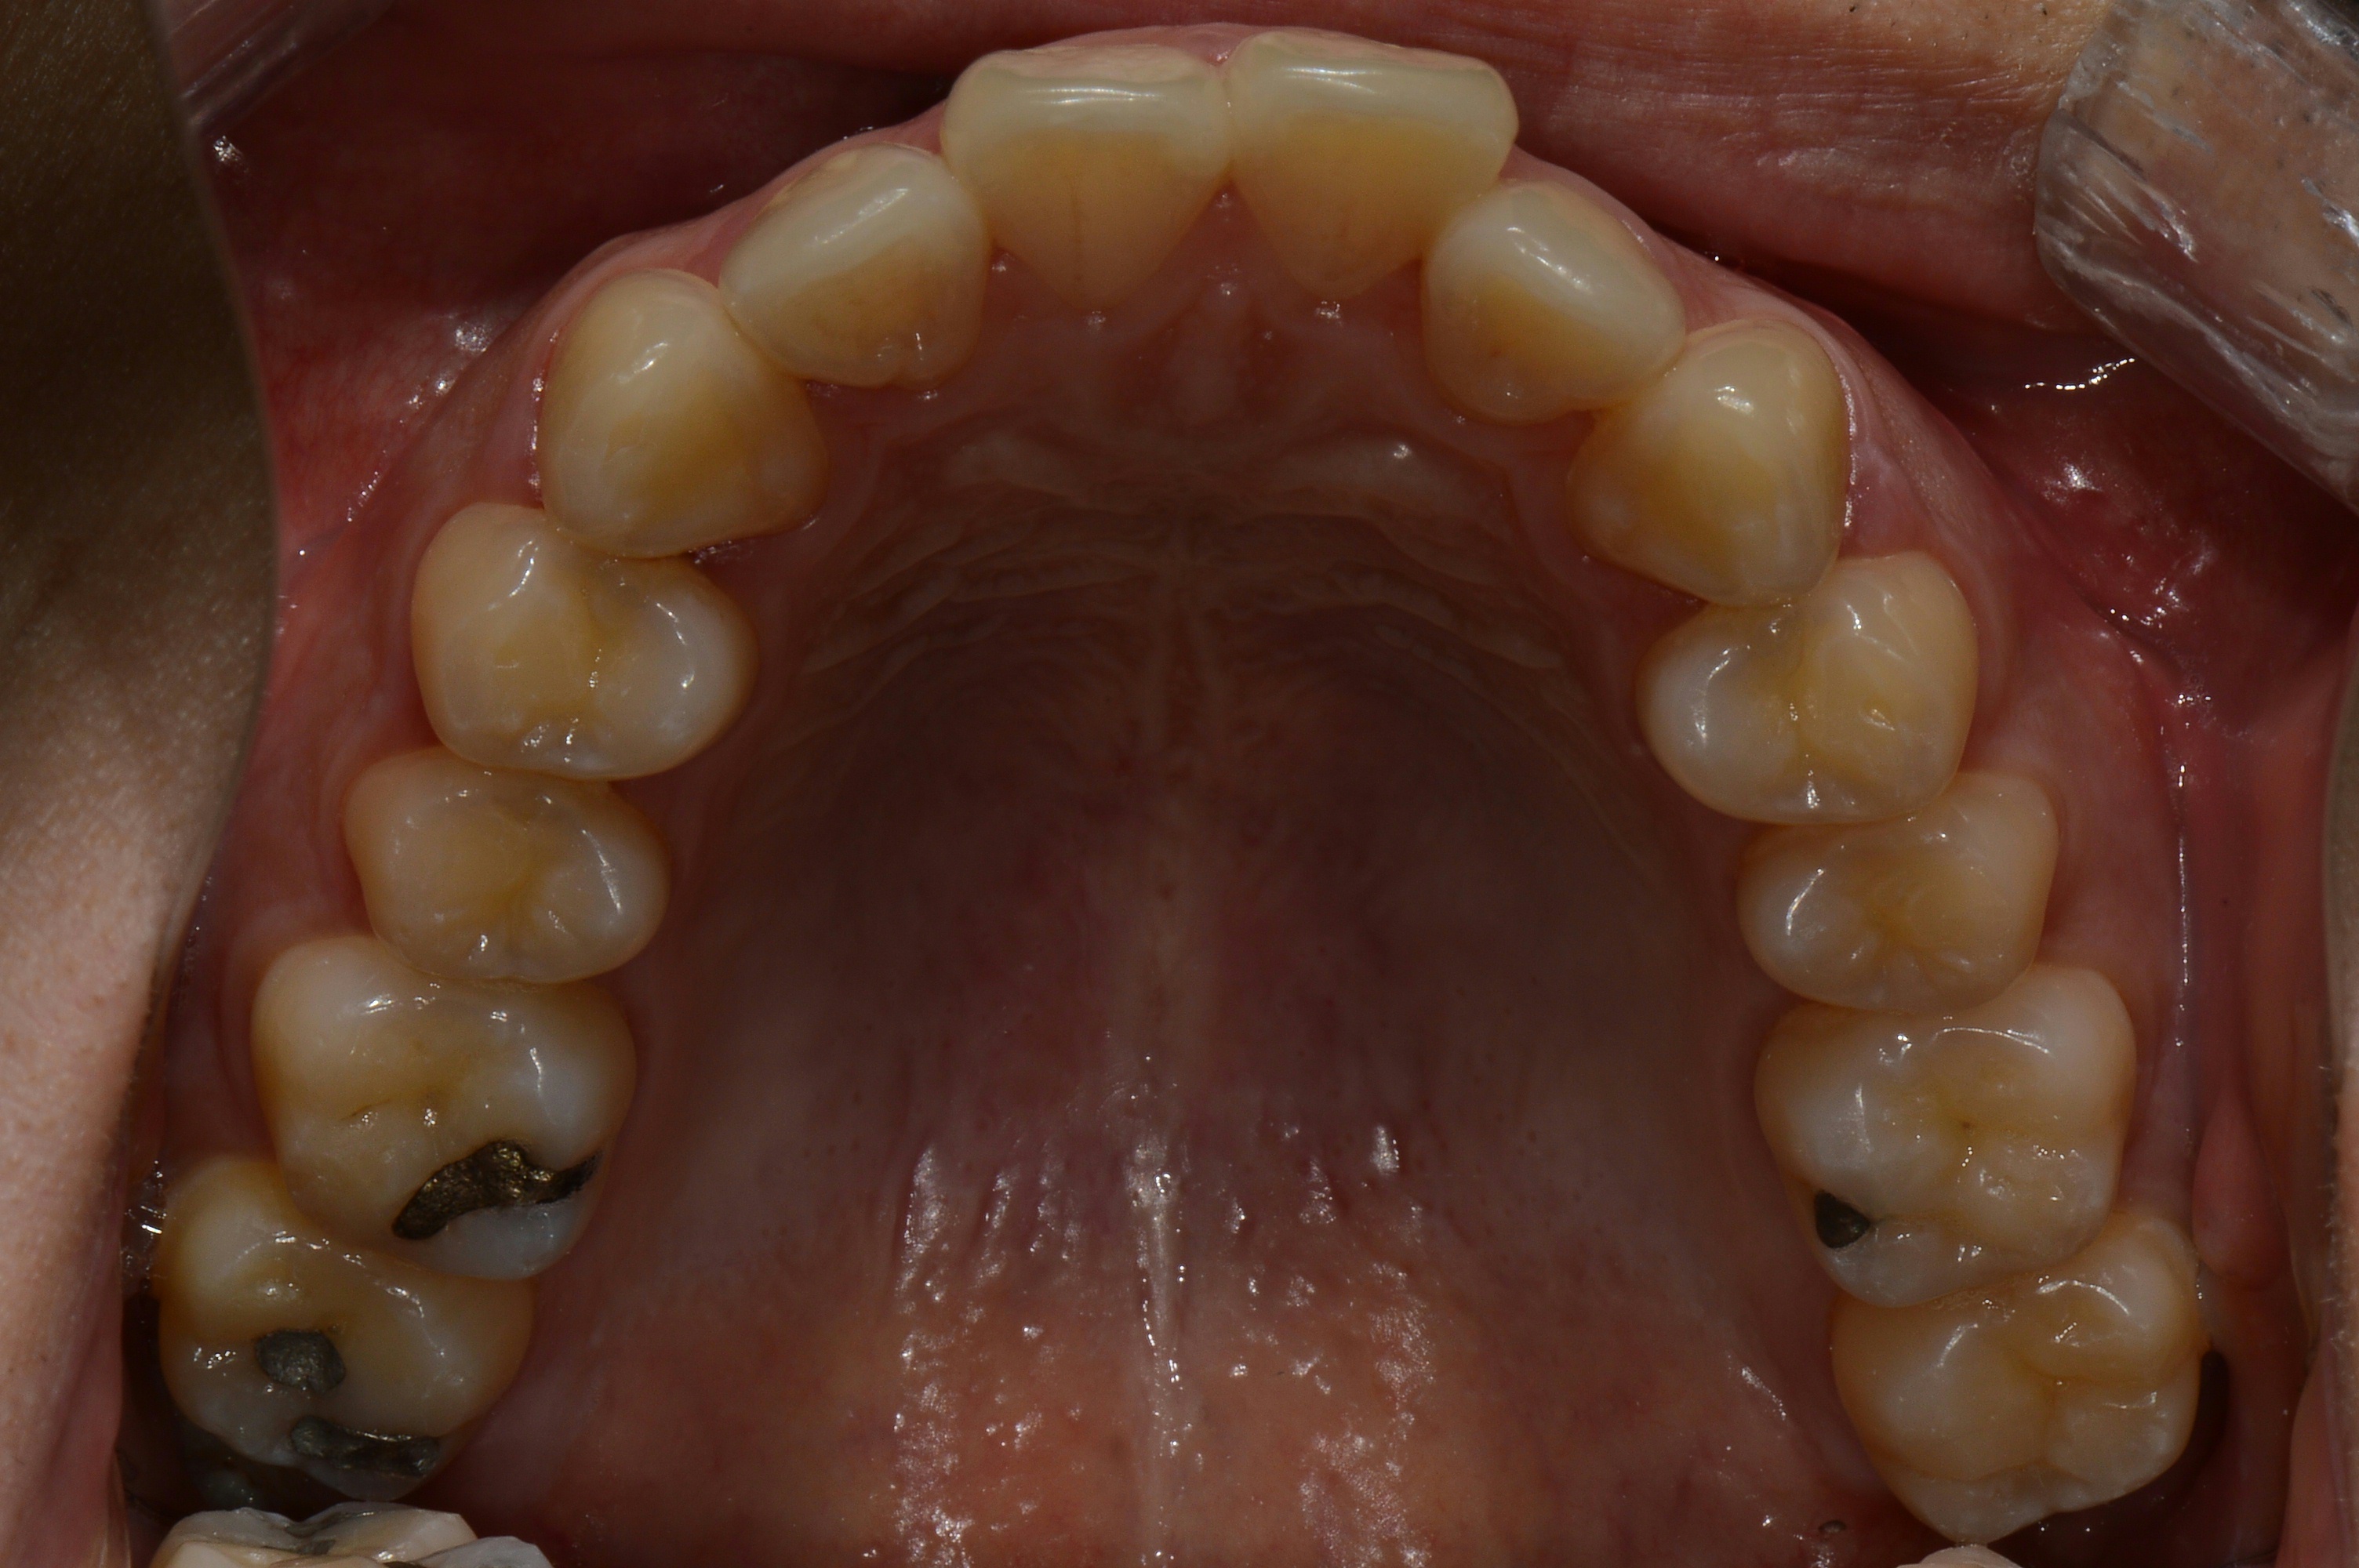

치료 후 사진입니다.